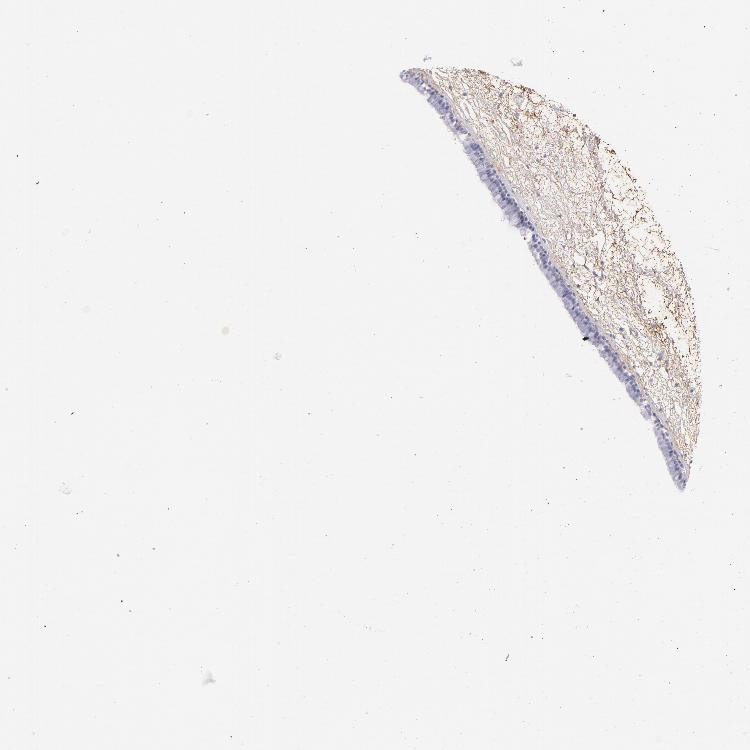

TISSUE PRIMARY DATA NASOPHARYNX Show tissue menu

NASOPHARYNX - Antibody stainingi

Antibody staining in the annotated cell types in the current human tissue is reported as not detected, low, medium, or high, based on conventional immunohistochemistry profiling in selected tissues. This score is based on the combination of the staining intensity and fraction of stained cells.

Each image is clickable and will lead to virtual microscopy that enables deeper exploration of all samples and also displays staining intensity scores, fraction scores and subcellular localization as well as patient and tissue information for each sample.

Antibody HPA001900Antibody HPA001901Antibody CAB008624

Respiratory epithelial cells Not detectedNot detectedMedium